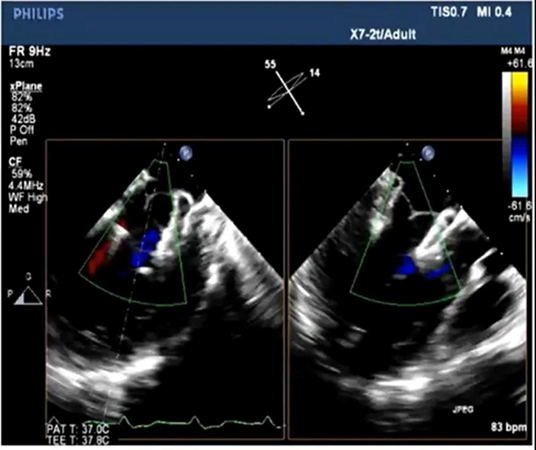

瓣膜释放后,TEE显示反流消失